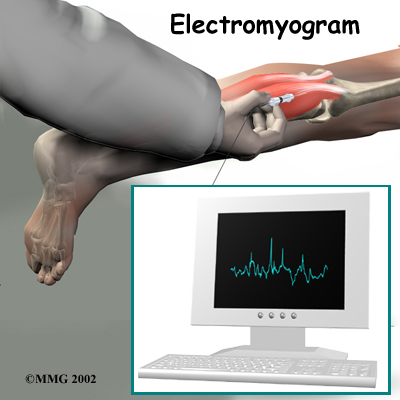

When there is a concern about neurologic problems, doctors may recommend electrodiagnostic tests of the nerves that go to the legs and feet. An electromyogram (EMG) checks whether the motor pathway of a nerve is working correctly. Motor impulses travel down the nerve and work to energize muscles.

Doctors may also order a somatosensory evoked potential (SSEP) test to locate more precisely where the spinal nerves are being squeezed. The SSEP is used to measure nerve sensations. These sensory impulses travel up the nerve, informing the body about sensations such as pain, temperature, and touch. The function of a nerve is recorded by an electrode placed over the skin in the area where the nerve travels.